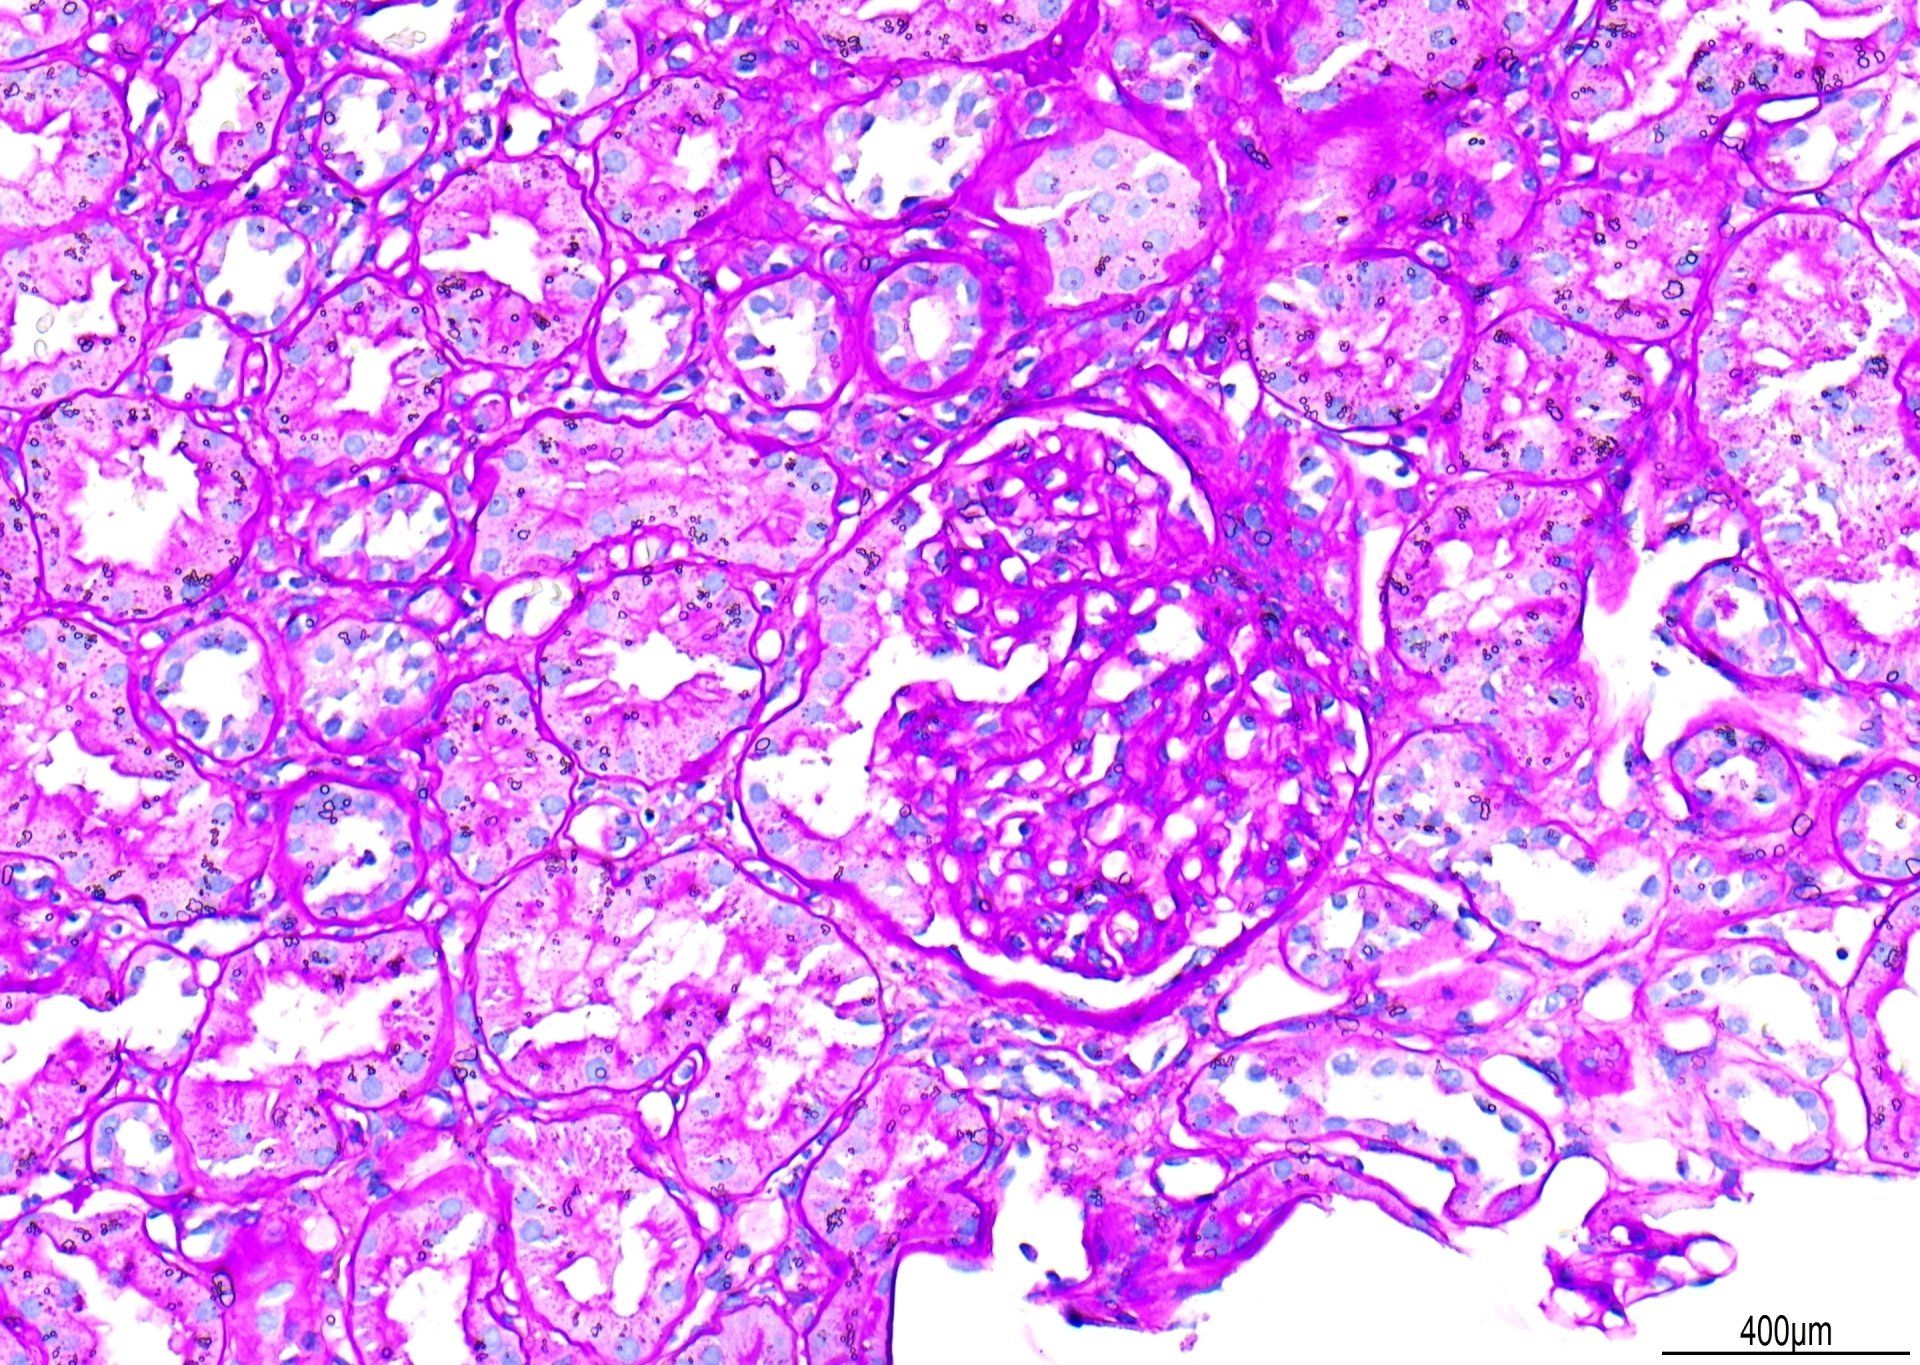

PAS - Nierskema

Gesien by x20, is dit 'n voorbeeld van 'n PAS-kleuring. Punte is afgetrek vir 'primêre agtergrondkleuring'. Alhoewel die glomerulêre basale membrane goed gekleur is, kan die kontras beter wees as daar minder agtergrond Schiff-kleuring was. Daarbenewens is waterdruppels onder die dekglas gesien. Die algehele telling vir hierdie afdeling het 7/10 behaal.